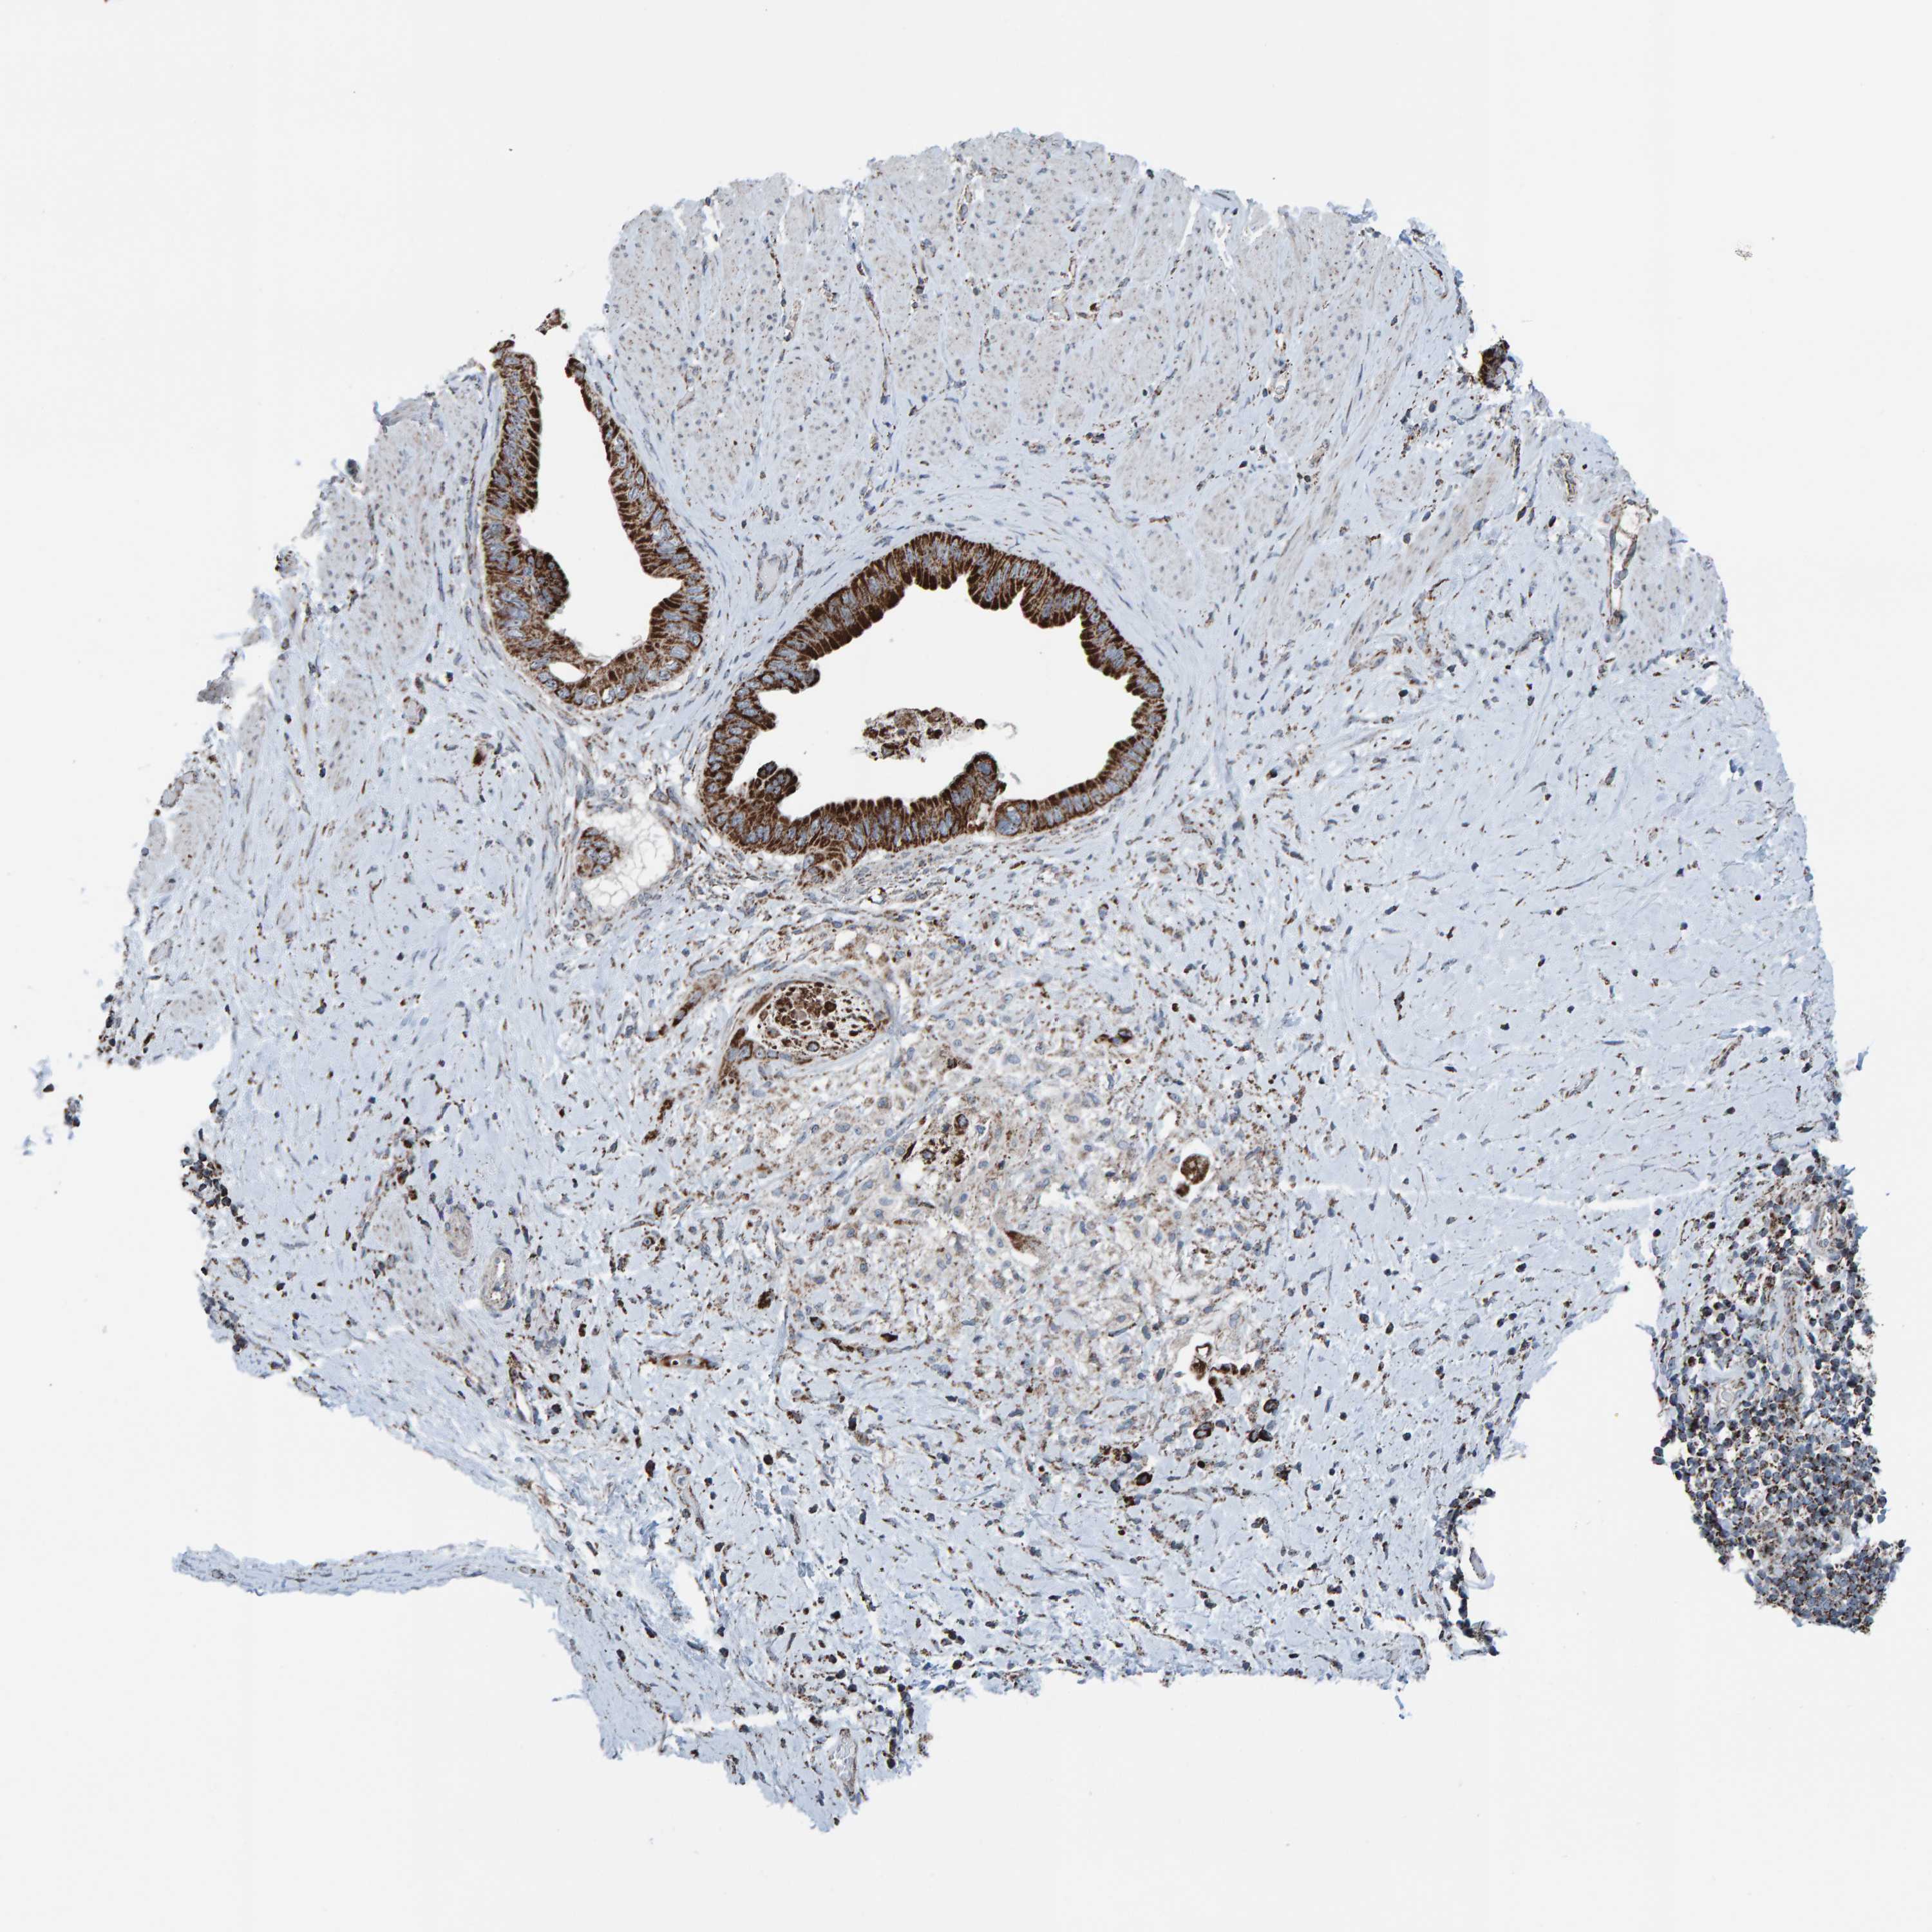

PANCREATIC CANCER - Protein expressioni

A mouse-over function shows sample information and annotation data. Click on an image to view it in a full screen mode. Samples can be filtered based on level of antibody staining by selecting one or several of the following categories: high, medium, low and not detected. The assay and annotation is described here.

Note that samples used for immunohistochemistry by the Human Protein Atlas do not correspond to samples in the TCGA dataset.

Antibody stainingi

Antibody staining in the annotated cell types in the current human tissue is reported as not detected, low, medium, or high, based on conventional immunohistochemistry profiling in selected tissues. This score is based on the combination of the staining intensity and fraction of stained cells.

Each image is clickable and will lead to virtual microscopy that enables deeper exploration of all samples and also displays staining intensity scores, fraction scores and subcellular localization as well as patient and tissue information for each sample.

Antibody HPA023806

Staining

High

Medium

Low

Not detected

Intensity

Strong

Moderate

Weak

Negative

Quantity

>75%

75%-25%

<25%

None

Location

Nuclear

Cytoplasmic/membranous

Cytoplasmic/membranous,nuclear

Adenocarcinoma, NOS